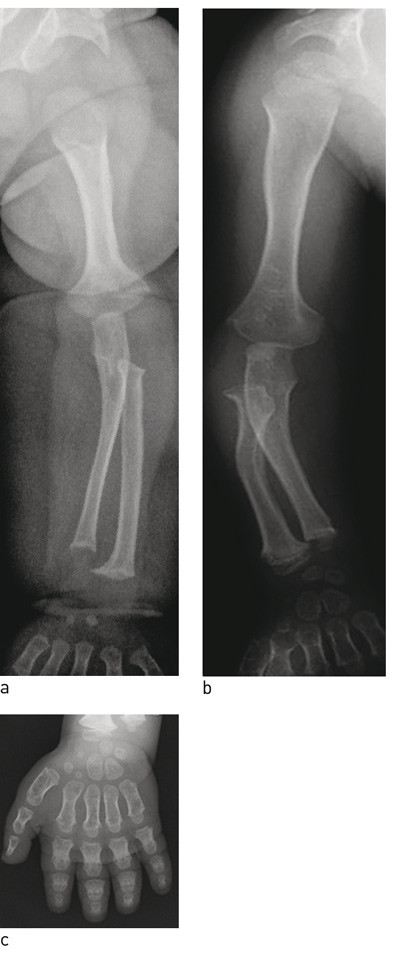

Antropometriske målinger er spesielt viktig ved tilstander som debuterer etter nyfødtalder. De omfatter lengde/høyde, vekt, hodeomkrets, sittehøyde og armspenn, men kan også omfatte andre kroppsmål som underarmslengde, håndstørrelse, legglengde og fotstørrelse. Slike målinger kan identifisere rhizomeliske former (korte overarmer/lår), mesomeliske former (korte underarmer/legger) og akromeliske former (korte hender/føtter) (fig 1).